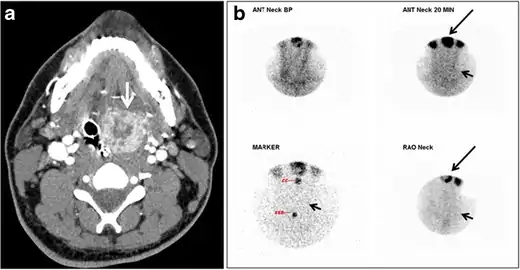

Fig. 16. Midline ectopic thyroid with Hashimoto's thyroiditis in a 49-year-old female patient. a Transverse greyscale ultrasound shows a 1.6 × 0.8 cm solid, well-defined, heterogeneous area (white arrow) in the midline, superior to the thyroid gland. It is iso-echogenic to the thyroid gland with no definite connection to the thyroid gland. b Transverse colour Doppler ultrasound shows significant increase in vascularity. c Axial enhanced neck CT scan at the level of thyroid cartilage demonstrates midline infrahyoid hyperdense soft tissue mass (white arrow) embedded within the strap muscle.[1]